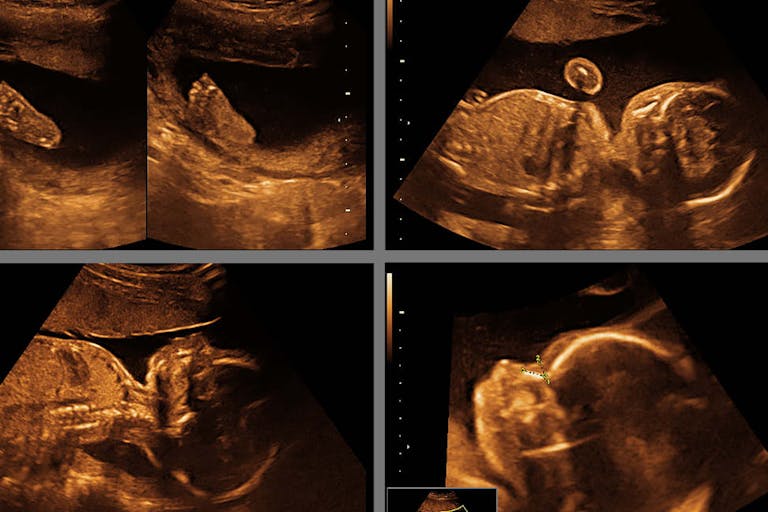

“Everything was great until the day of my anatomy ultrasound at 20 weeks,” she said. “I was at home waiting for my appointment later that afternoon. I had the weekend before — a few days before — had had some increased discharge, mucousy stuff. I called my doctor. I was evaluated, everything looked fine at that point. Stay at bed rest for two days.”

But then, three hours before her scheduled appointment, she felt “massive pressure” and knew what it meant — the amniotic sac had dropped. She knew it was an emergency. She went to the hospital by ambulance; doctors, whom she knew, attempted to “push the membranes back and put in an emergency cerclage — and I knew I was screwed before I even went to the OR because I saw my own ultrasound — my water broke.”

“So now, I’m 20 weeks with ruptured membranes with twins. They both have heart rates. You couldn’t possibly have more informed consent than I have and know the risks of everything. It was a fully-desired pregnancy. There was nothing wrong with me or the twins. My waters broke.”